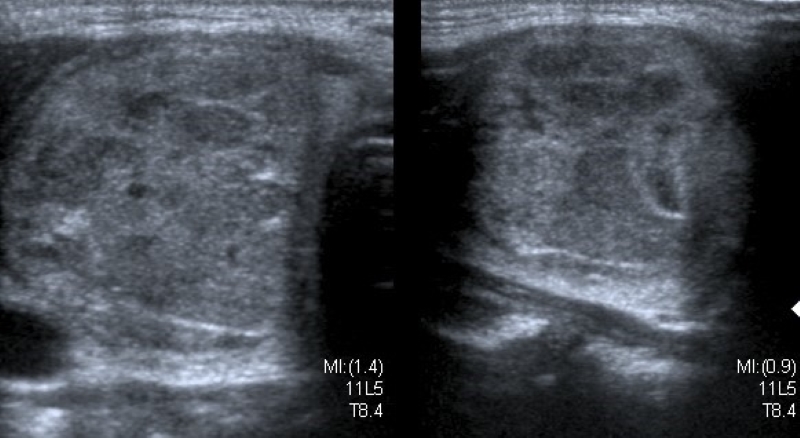

Describe el componente interno del nódulo, identificando la presencia de contenido sólido (Fig. 1) o quístico (Fig. 2), y en los casos de nódulos mixtos (Fig. 3) la proporción de cada uno (predominantemente sólido/ predominantemente quístico). Cuando se evalúa un nódulo parcialmente quístico es importante caracterizar su componente sólido indicando además si tiene localización central o periférica (esta última podría asociarse con mayor riesgo de malignidad)13.

Los nódulos completamente quísticos son considerados benignos2,14,15) y los sólidos se asocian mayormente a malignidad15,16, pero hay descriptos nódulos sólidos benignos, como así también nódulos confirmados como CPT con componente mixto2,15,17.

Existen otro tipo de nódulos, los espongiformes, que presentan un patrón mixto con múltiples quistes pequeños en su interior, y tienen un muy bajo riesgo de Malignidad2,13,14,18.